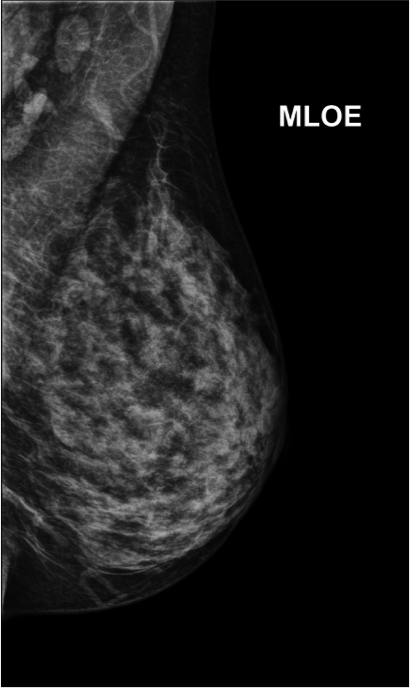

A mamografia evoluiu ao longo dos anos, passando da mamografia de alta resolução para a mamografia digital e recentemente para a mamografia digital com tomossíntese. A tomossíntese não é um novo exame, mas uma ferramenta disponível nos mamógrafos mais novos e modernos, onde se consegue gerar um tipo de imagem 3D, melhorando a detecção do câncer. Desta maneira, deve-se considerar incluir a mamografia com tomossíntese no rastreamento sempre que possível, ou disponível.

- o melhor método de imagem ainda é a mamografia digital e deve-se considerar incluir a tomossíntese (uma ferramenta dos melhores aparelhos de mamografia) no rastreamento sempre que possível, ou disponível;

A densidade maior ou menor da mama ganha importância na análise da mamografia. Nesse momento, o médico radiologista precisa determinar o quão densa é a mama e para isso a classifica segundo 4 categorias que variam de mamas extremamente densas a mamas extremamente adiposas. Quanto mais densa é a mama, mais branca ela aparece na mamografia. Sabendo-se que lesões mamárias (incluindo o câncer) também são brancas na mamografia, conseguimos entender que quanto mais densa a mama, mais difícil é a leitura desse exame pelo médico e, portanto, mais fácil é uma lesão ou outra passar desapercebida.

Esse fato, em conjunto com os dados da literatura de que a alta densidade mamária pode aumentar o risco de câncer de mama em torno de 1,2 a 2 x (comparado com a média), tornam a mulher com mamas densas foco de especial atenção dos médicos. Nesse grupo de mulheres, é fundamental uma análise minuciosa e muitas vezes a complementação da mamografia com a tomossíntese (mamografia 3D), ultrassonografia ou, em casos específicos, a ressonância magnética.

Tomossíntese (ou mamografia 3D) é uma nova tecnologia de imagem digital da mama, com baixa dose de radiação. O exame é realizado no mesmo aparelho de mamografia digital e o tempo de duração é praticamente o mesmo. A mama é comprimida como na mamografia convencional, em posição mediolateral oblíqua. Em seguida, é feita uma varredura de toda a mama (o tubo de RX movimenta-se em ângulo pré-determinado, como um arco), gerando várias imagens que serão imediatamente transmitidas ao computador para reconstrução. O médico radiologista poderá avaliar todas as imagens geradas na estação de trabalho.

Estudos têm mostrado que a tomossíntese reduz significantemente a superposição dos tecidos da mama, sobretudo em mamas mais densas, melhorando a identificação de lesões e permitindo diferenciar lesões verdadeiras daquelas que seriam geradas por esta superposição dos tecidos normais. Com isso, há uma menor reconvocação das pacientes para estudo complementar e uma redução expressiva do número de resultados falso-positivos e biópsias desnecessárias. Outra grande vantagem da tomossíntese é a maior sensibilidade em detectar microcalcificações e tumores invasivos em estágio inicial.

Publicações recentes mostram que a tomossíntese, associada à mamografia digital nos exames de rastreamento, resulta em uma taxa de detecção do câncer mais elevada, além do diagnóstico de maior número de tumores invasivos, quando comparada ao uso da mamografia convencional.